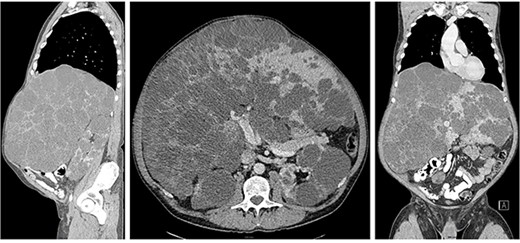

Liver transplantation was performed on 11th of July 2022: massive hepatomegaly (Fig. 2) and extensive adhesions due to previous laparotomy and inicisional hernia repair made the release of the recipient’s liver very difficult. The duration of the operation was 413 minutes, the anhepatic time was 73 minutes, and the cold ischemia of the donor liver was 517 minutes. In the final histology, the liver measures were 53 x 37 x 39 x 16 cm and weight 14,75 kg (Fig. 3). Histologically, it was an adult polycystic kidney disease with liver involvement (polycystic liver disease), there were no signs of malignancy.

Massive hepatomegaly and previous operations made mobilization of the liver very difficult.